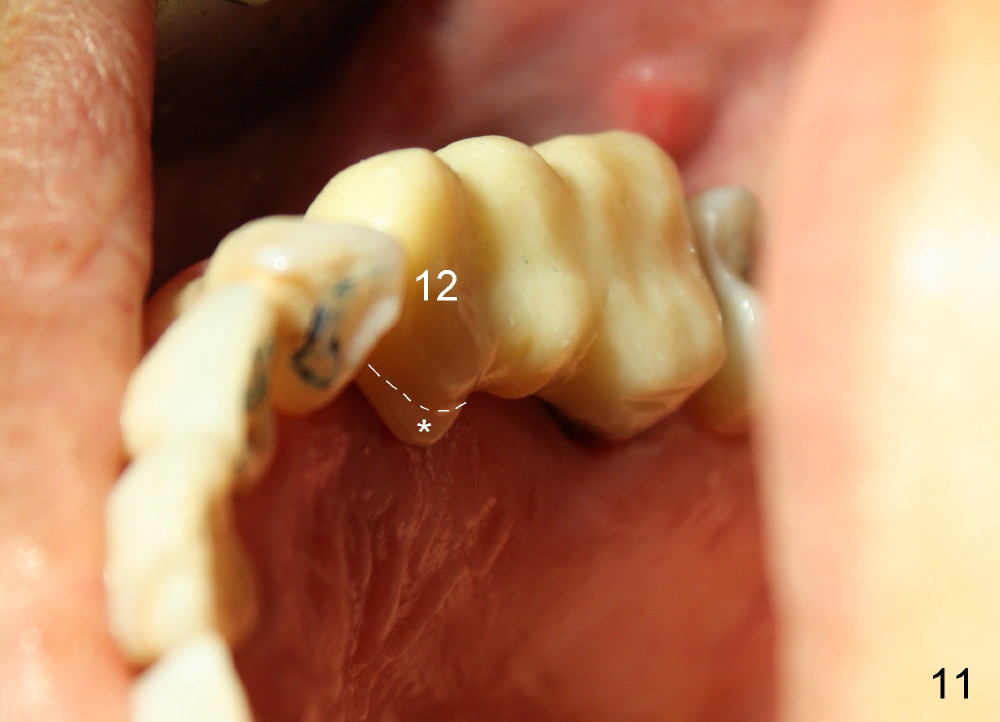

Buccal to #14 implant/abutment is a large defect, which is filled with allograft and Osteogen and covered by collagen membrane (Fig.9 M). The defect at the site of #12 is mesiopalatal, which is repaired in the same fashion (Fig.10: M). The collagen membrane is in turn protected by the "overhang" (extension) of the immediate provisional bridge (Fig.11,12 *). Once the wounds heal (Fig.13, 9 days postop), the extension is trimmed (Fig.14).